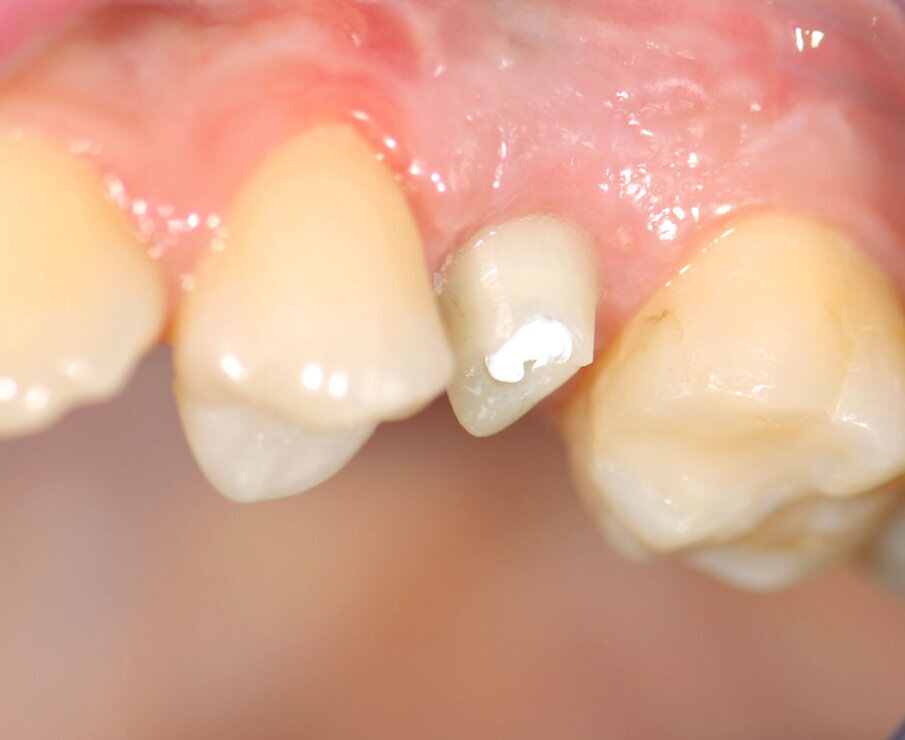

Paziente: donna, 31 anni, in buona salute.

Situazione clinica: primo premolare superiore sinistro non recuperabile dopo due precedenti resezioni radicolari, corona fratturata.

La paziente presentava un primo premolare superiore sinistro non recuperabile. La CBCT mostra la situazione iniziale (Fig. 1). Si noti quella che appare come una grande fenestrazione buccale nell’area della resezione radicolare (Fig. 2). Il dente fratturato è stato estratto (Figg. 3, 4). Lo scollamento del lembo di accesso rivela la fenestrazione buccale (Fig. 5). L’osteotomia è stata preparata secondo il protocollo di fresatura di Neoss ProActive Edge (Fig. 6). Successivamente viene posizionato un impianto Neoss ProActive Edge Ø 5.0 × 13 mm (Fig. 7). L’impianto è stato posizionato in una situazione di disponibilità ossea molto limitata e densità ossea media (Fig. 8). Nonostante le limitazioni dovute alla condizione ossea, è stata raggiunta una buona stabilità primaria. È stato utilizzato un torque di inserimento di 20 Ncm, l’ISQ è risultato in un range di 70/77. Per correggere la fenestrazione buccale è stato eseguito un innesto con particolato osseo di origine porcina (Fig. 9). L’innesto osseo è stato coperto con una membrana di collagene riassorbibile (Fig. 10). Il lembo mucoso è stato suturato attorno al pilastro di guarigione in PEEK, consentendo la guarigione in una sola fase (Fig. 11).